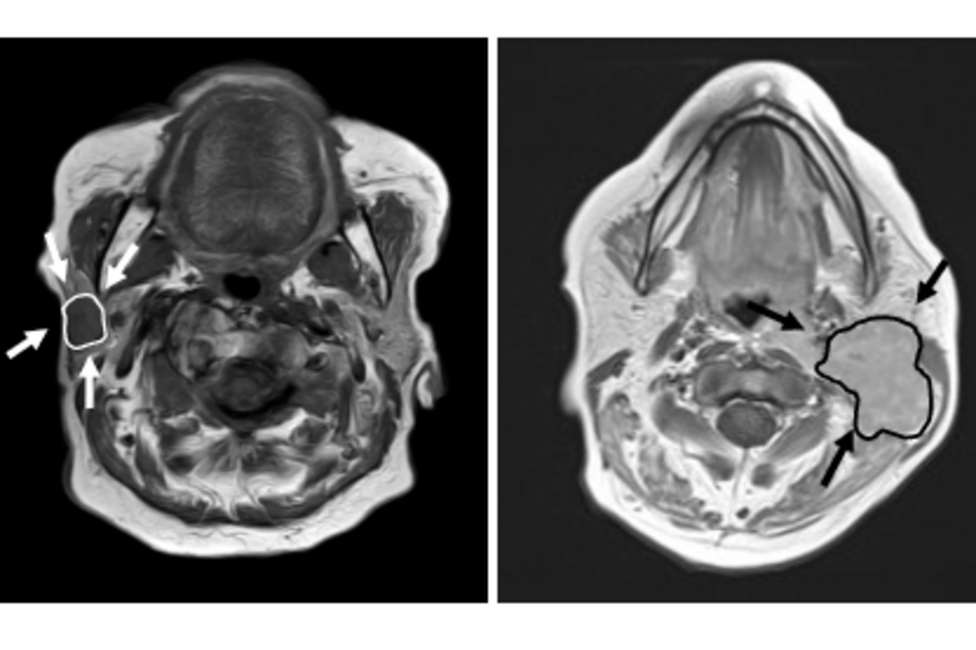

Im Rahmen der Erstbegutachtung in der allgemeinen HNO-Ambulanz (vorzugsweise Montag oder Mittwoch) erfolgt eine erste Diagnostik und Abklärung. Bei Verdacht auf Raumforderungen/Tumore in den Speicheldrüsen (siehe Abbildung) kann eine weiterführende bioptische Abklärung indiziert und auf der HNO-Klinik durchgeführt werden.

Die häufigsten Tumore (ca. 80%) befinden sich in der Ohrspeicheldrüse (Parotis) und sind benigne (gutartig). Im Rahmen einer operativen Sanierung (Parotidektomie) werden diese Tumore entfernt, wobei spezielles Augenmerk auf den Gesichtsnerv (N. Fazialis) gelegt wird, welcher durch die Ohrspeicheldrüse zieht.